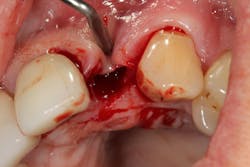

Related video: Extraction and socket grafting in preparation for dental implant placement

This surgical video demonstrates removal of a tooth with loss of buccal plate and grafting of the remaining socket with Geistlich Bio-Oss Collagen and Geistlich Bio-Gide to preserve the ridge for implant placement.